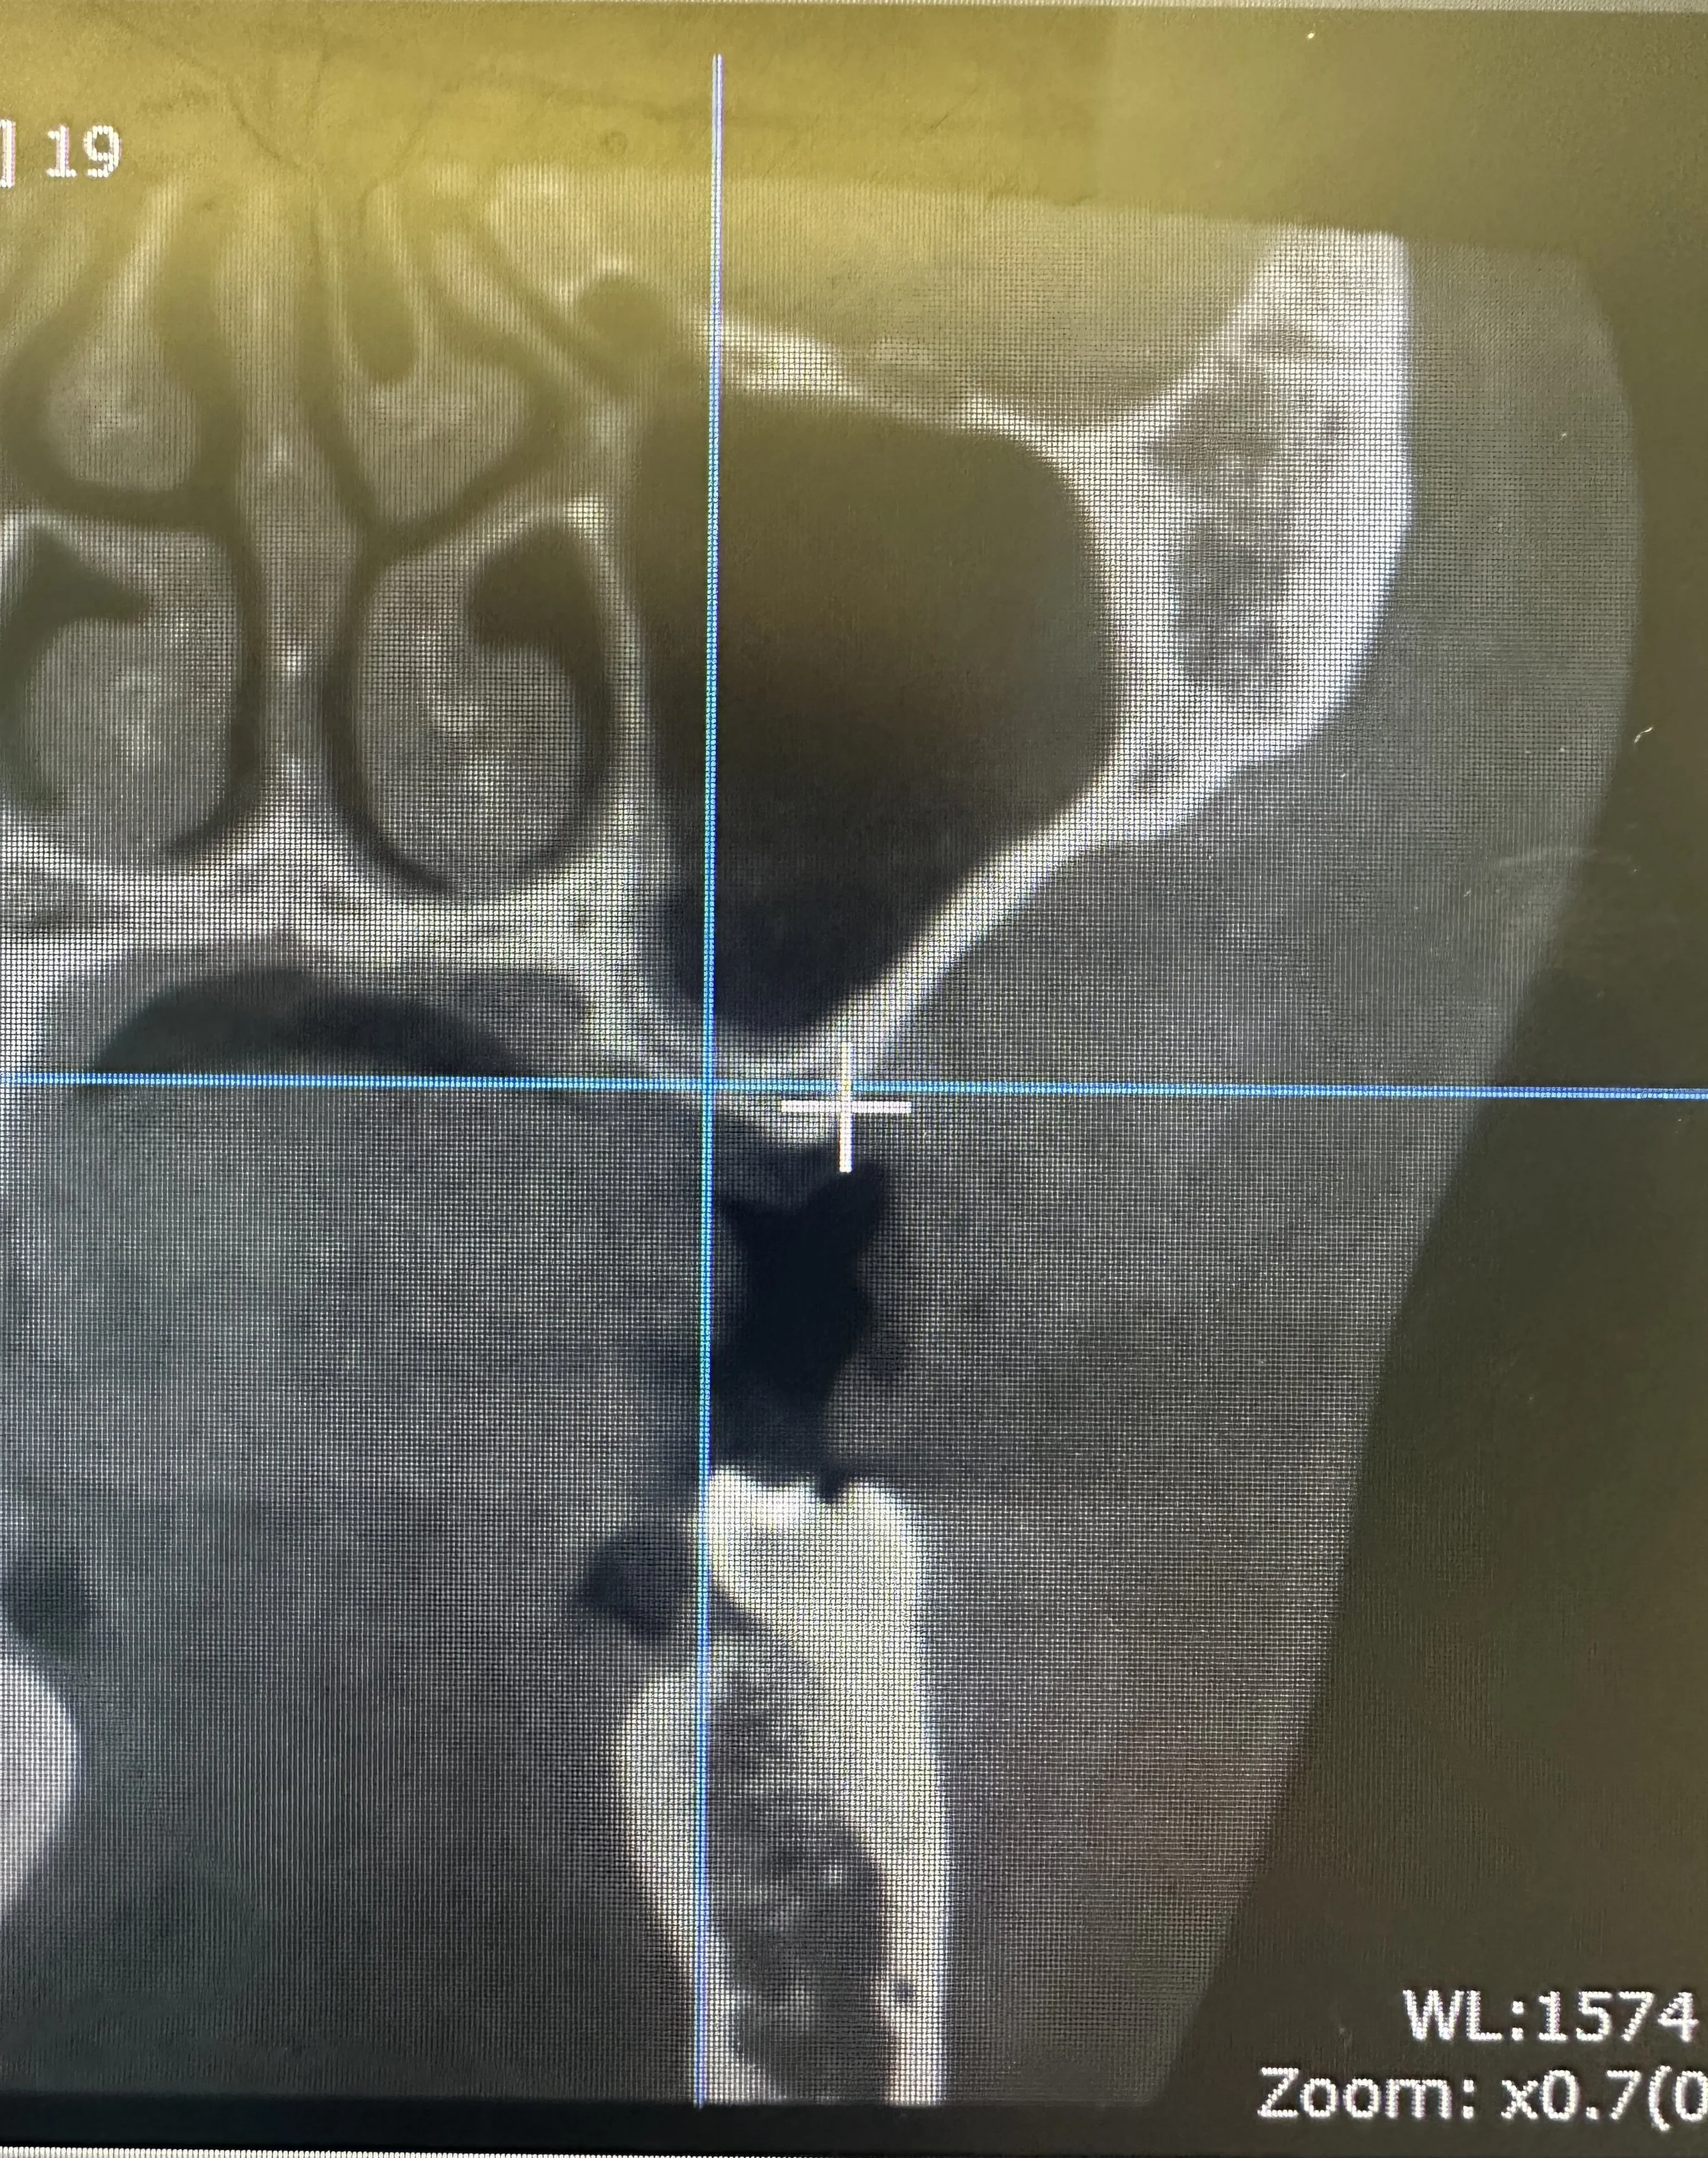

In this case, the patient presented with reduced vertical bone height in the upper left posterior region, making implant placement at site #14 unsuitable without prior augmentation. Advanced imaging confirmed the proximity of the maxillary sinus and the need for a staged surgical approach.

To restore the foundation for implant placement, a left maxillary lateral window sinus lift was performed. This technique allowed for controlled elevation of the sinus membrane and precise placement of bone graft material, increasing available bone volume while preserving surrounding anatomy.